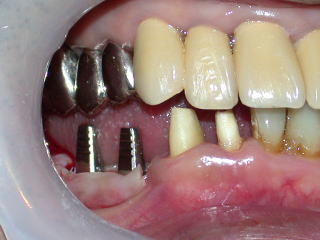

平成20年3月、インプラントの植立を行いました。

上下の隙間(補綴スペース)や近遠心、頬舌関係を良く調べます。

顎の上下関係、全体の位置付けも重要です。

目視で良く確認、レントゲンで位置をさらに良く確認します。

インプラントの位置が、良い位置に植立されたのを確認し、4糸縫合しました。

インプラント固定用の仮歯を装着し、抗生物質などを処方し、インプラント植立を終了します。